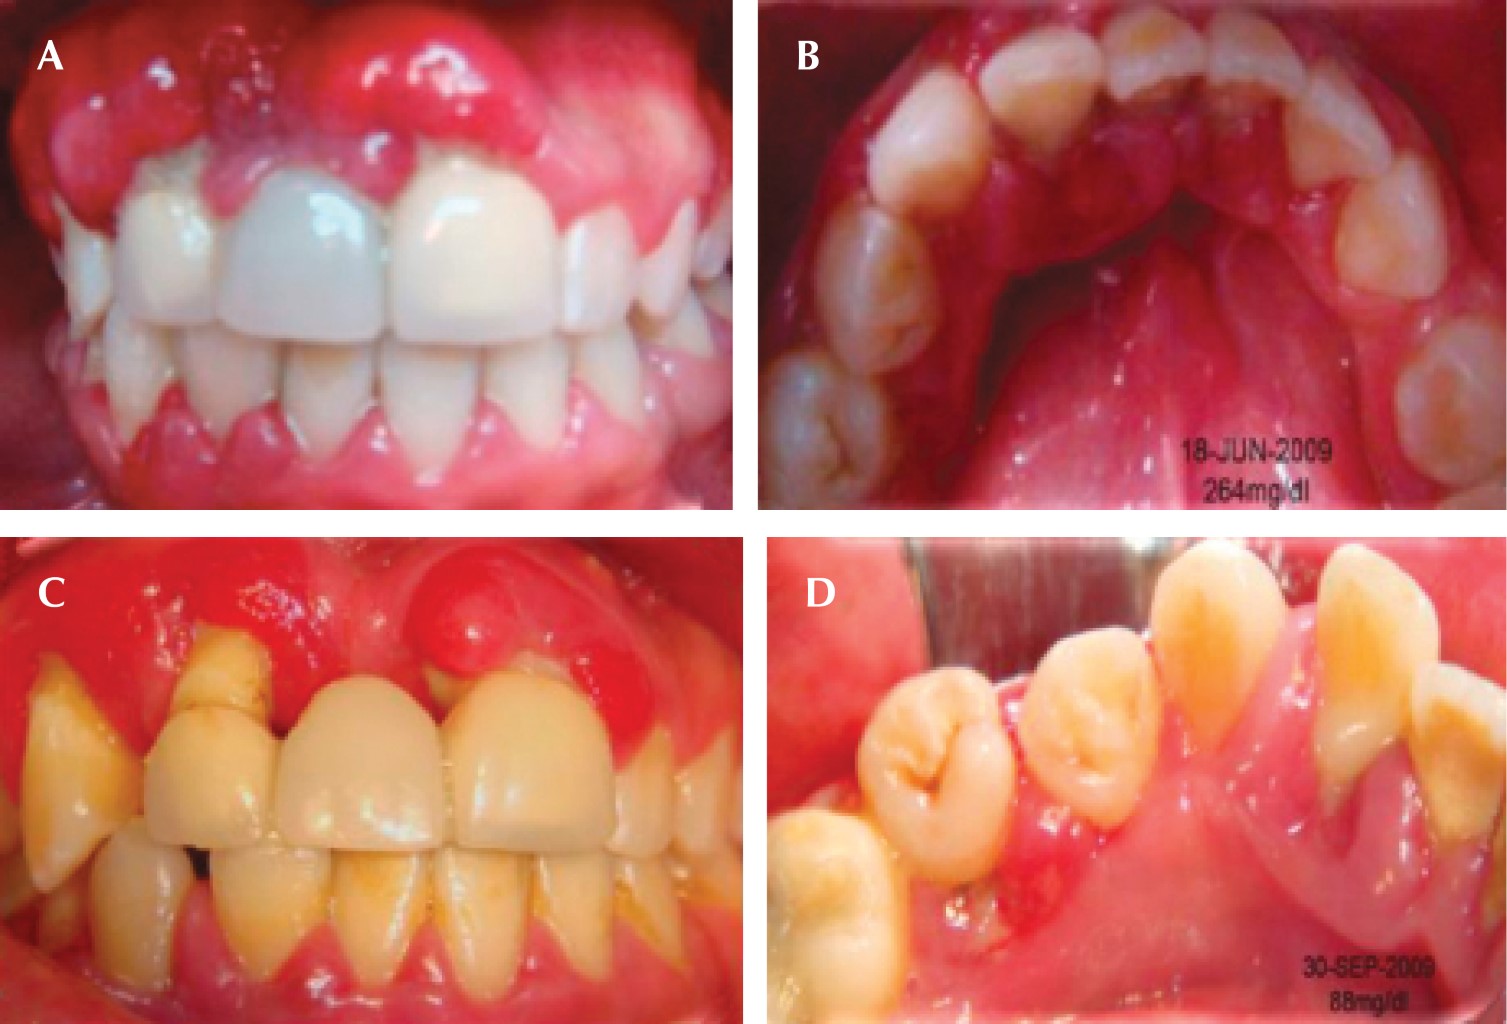

A la inspección clínica se observa agrandamiento gingival en la zona anterior superior (Figura 1A), múltiples abscesos periodontales (Figura 1B), presencia de biofilm microbiano, cálculo supragingival y subgingival. Durante el examen periodontal se encontraron profundidades al sondaje de 5, 7 y hasta 13 mm y movilidad grado II, en la evaluación radiográfica se observó reabsorción ósea generalizada (Figura 1C y D).

Posterior a la evaluación clínica y radiográfica se decidió realizar interconsulta con el Hospital General "Dr. Manuel Gea González" para confirmar diagnóstico sistémico y adecuar terapia, la paciente se diagnosticó como diabética tipo 2, modificando el medicamento, eliminando insulina y prescribiendo metformina con glibenclamida.

Con los elementos obtenidos se realizó el diagnóstico periodontal:

• • Periodontitis etapa IV generalizada grado C.

• • Agrandamiento gingival crónico de tipo inflamatorio.

• • Absceso periodontal agudo.

Una vez establecido el diagnóstico, se emitió el plan de tratamiento que consistió en realizar una fase I periodontal, alternando sus citas con el Hospital "Dr. Manuel Gea González" para el control de su glicemia. Después de modificar el tratamiento para la diabetes por parte del Hospital y realizando el control mecánico del biofilm microbiano, se comenzaron a observar cambios clínicos, como disminución del aumento de volumen (Figura 2A y C) y desaparición de los absceso periodontales (Figura 2B y D). Una vez que los niveles de glucosa se estabilizaron, se inició la fase II del nivel de tratamiento periodontal (extracciones, desbridamiento por colgajo con injerto óseo), se medicó a la paciente con doxiciclina (previo al procedimiento quirúrgico una cápsula de 100 mg cada 12 horas, segundo día hasta el séptimo día, una cápsula de 50 mg cada 12 horas) y ketorolaco de 10 mg, una tableta cada ocho horas o sólo en caso de dolor. Después de estabilizar periodontalmente a la paciente se incorporó a la terapia de mantenimiento y se dio inicio el tratamiento de rehabilitación, elaborando una prótesis parcial removible (Figura 3A-C). Después de dos años de adhesión al tratamiento, la paciente dejó de asistir a consulta.